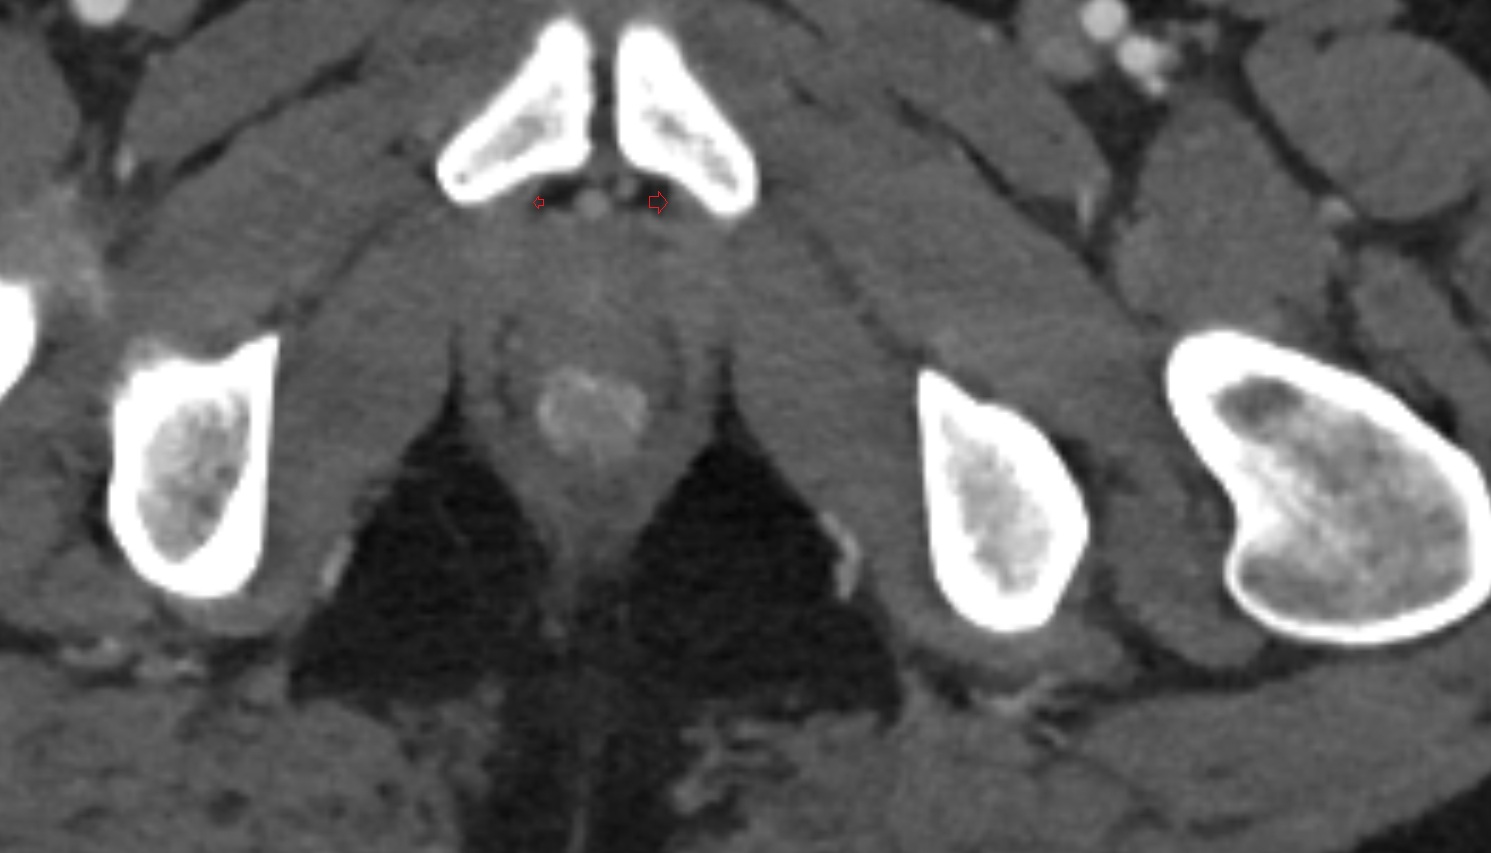

- Peripheral zone of prostate

- Anterior Fibromuscular Stroma of prostate

- Central zone of prostate

- Transitional zone of prostate